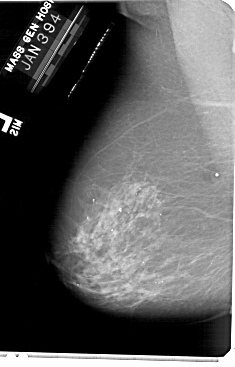

A_1901_1.RIGHT_MLO

RIGHT_MLO LINES 5491 PIXELS_PER_LINE 3721 BITS_PER_PIXEL 12 RESOLUTION 43.5 OVERLAY